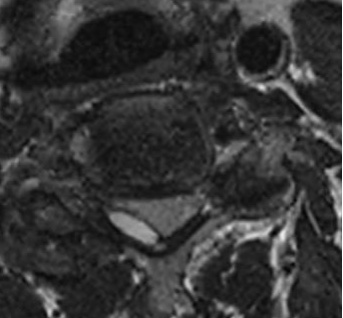

近日,奉贤区中心医院多学科团队紧密协作,成功救治一名因颈椎椎管内占位伴血肿形成、突发剧烈臂痛险些瘫痪的六旬患者。经精准诊断、精细手术及系统康复,患者一周内顺利康复出院,彰显区域医疗中心急危重症救治能力。 患者王老伯数日前突发右上臂剧烈放射性疼痛,右侧肢体迅速无力,持物、行走均受严重影响,病情进展极快。家人紧急将其送至区中心医院就诊。经初步检查,医生高度怀疑为颈椎椎管内占位性病变伴血肿形成。该病若脊髓长期受压,极易造成不可逆神经损伤,甚至导致瘫痪。 区中心医院随即启动多学科会诊(MDT),集结骨科、神经外科等相关科室专家进行联合评估。 神经外科团队率先为患者施行脊髓血管造影,明确病灶位置与范围,排除脊髓血管畸形的可能,为后续手术方案的制定提供了精准依据。 然而术前评估带来了新难题:王老伯还合并有睡眠呼吸暂停综合征与阻塞性肺病,这增加了手术与麻醉的风险。呼吸与危重症医学科随即为其量身定制了呼吸调理方案,并指导术前呼吸训练;耳鼻咽喉科协助排查气道梗阻隐患,优化呼吸道管理策略。在多学科协作下,王老伯的呼吸功能被调整至可耐受手术的状态。 颈椎手术被誉为脊柱外科“皇冠上的明珠”。颈椎椎管内部空间狭窄,神经结构密集,加之肿物与神经粘连紧密,手术操作难度极大。骨科林在俊主任医师团队综合多学科会诊意见,经过反复研讨,最终制定了个性化的精细手术方案。 手术当天,麻醉科团队精准实施麻醉,并全程动态监测患者生命体征;手术室护理团队默契配合,严格执行无菌操作,为手术安全保驾护航。在多学科团队的紧密协作下,林在俊主任医师在手术显微镜下以毫米级精度逐步操作,完整清除了肿物及血肿,并切开硬膜进行探查,确保无病灶残留。手术在最大程度保护神经功能与脊柱稳定性的前提下顺利完成,术中出血少,创伤小。 术后第二天,患者臂痛明显缓解,可自主翻身、抬手。疼痛理疗科同步开展个体化康复训练,术后一周,患者已能独立行走、生活自理,顺利康复出院。 专家提醒:这些信号别当“小毛病” 颈肩腰腿痛不可轻视。如出现突发剧烈疼痛、肢体麻木无力、步态不稳等症状,可能是椎管内病变信号,务必尽早到正规医院就诊,避免延误最佳治疗时机。 专家信息 各种复杂脊柱疾患的手术治疗及微创治疗。尤其擅长:脊柱肿瘤手术治疗及综合治疗;椎管内(外)肿瘤切除手术;各种颈、腰椎疾患(包括颈椎病、腰椎间盘突出症、椎管狭窄症、腰椎滑脱症等)及脊柱骨折的微创治疗。 奉贤区中心医院骨科 专家门诊信息一览 上海市第六人民医院 *根据出诊时间排序 奉贤区中心医院 *根据出诊时间排序 门诊预约电话 021-375385222(8:00—16:00)

更多精彩内容,请关注“美谷奉贤”APP

服务升级,就在家门口!四团镇镇西村“中医特色卫生室”提档升级、全新亮相!